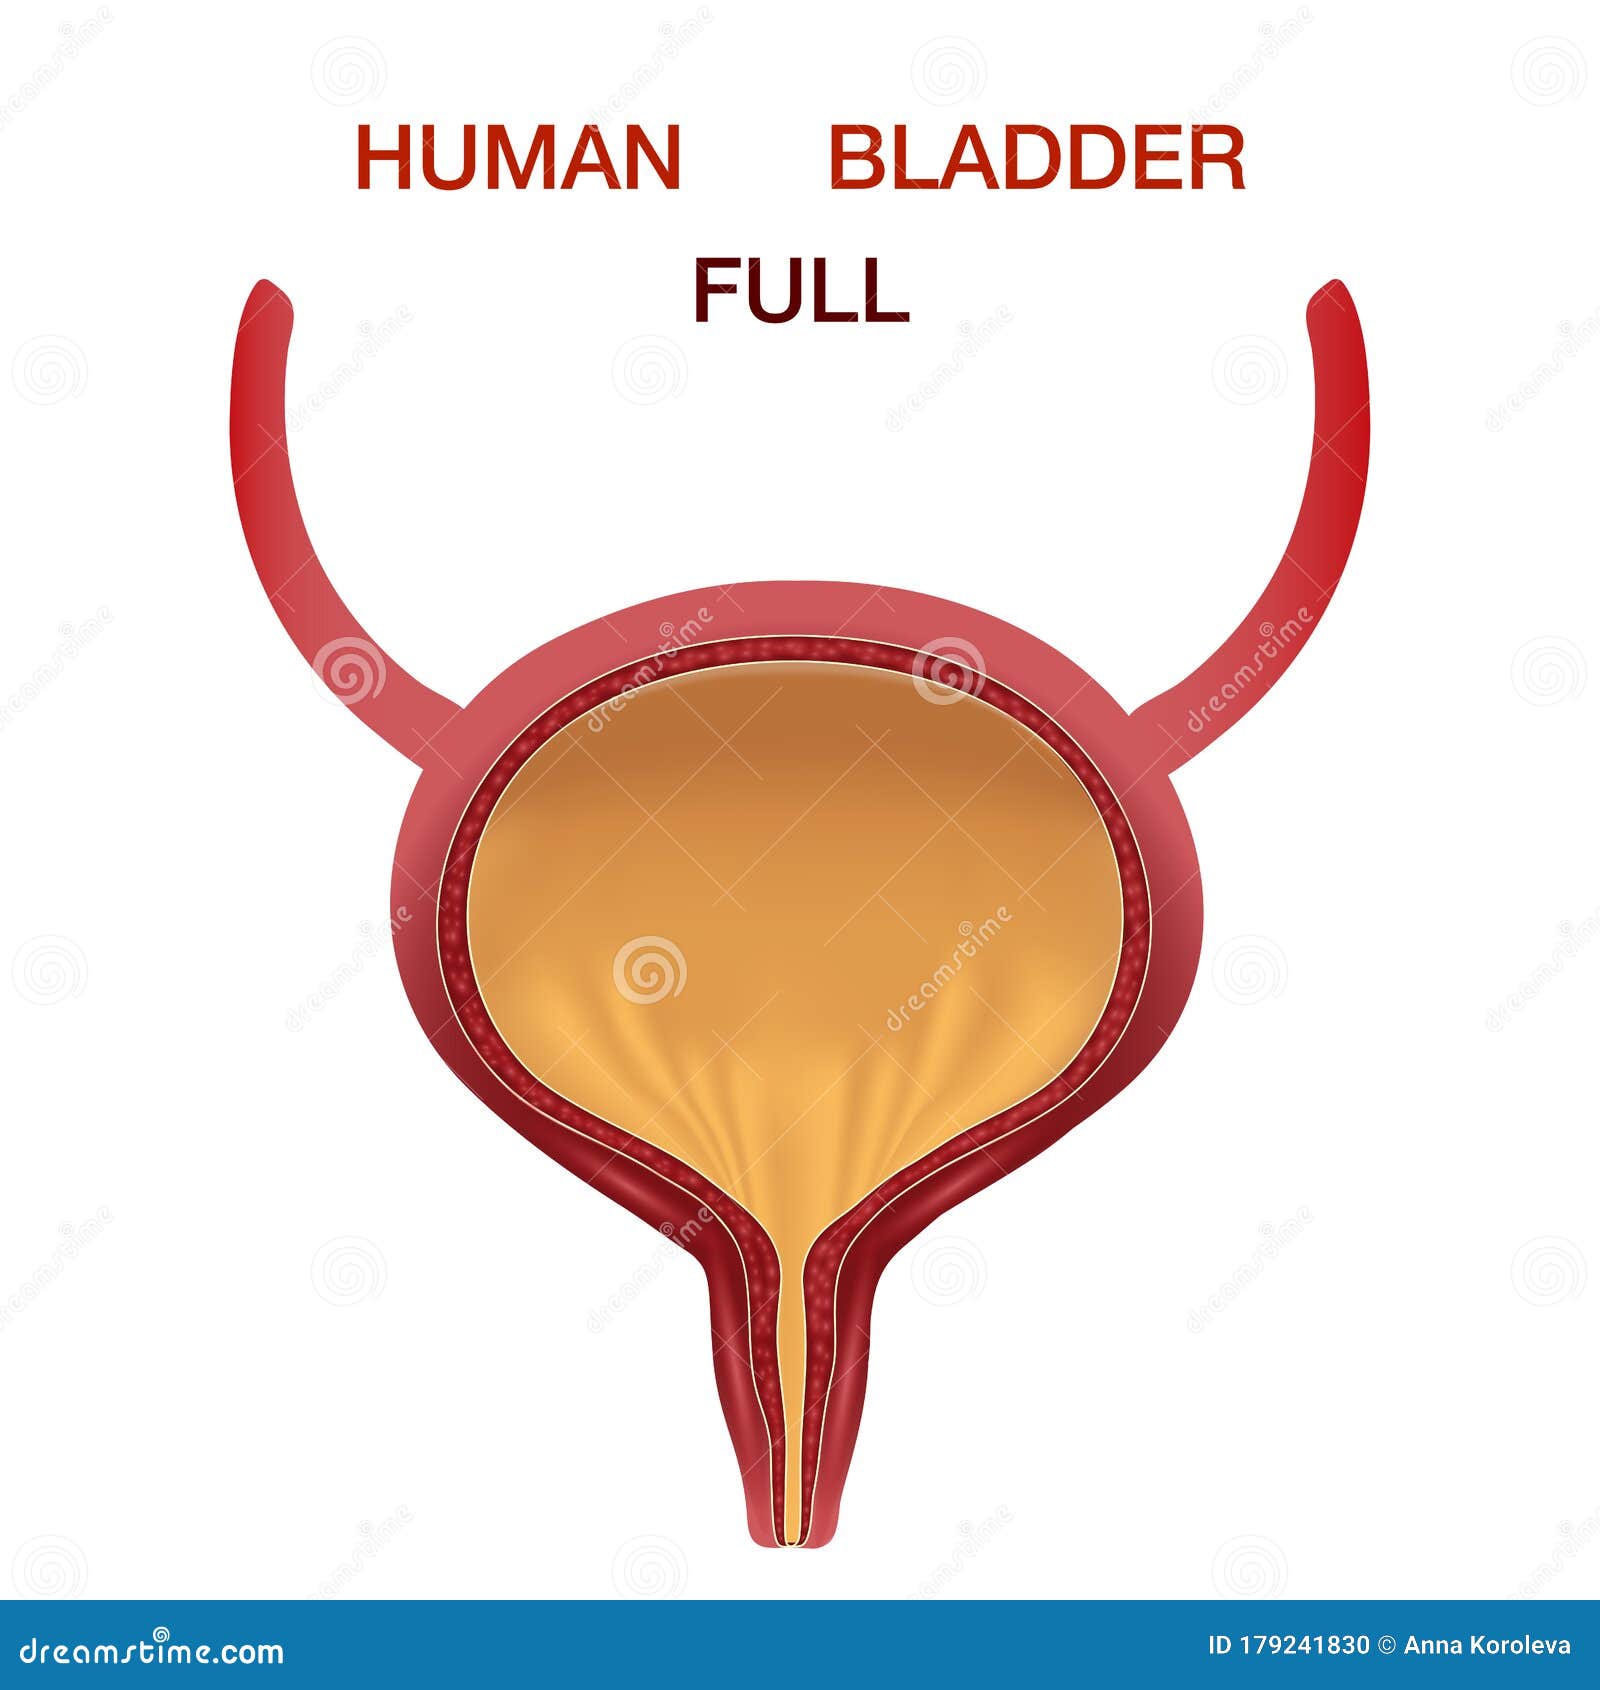

location of the bladder in the human body

Posts: location of the bladder in the human body